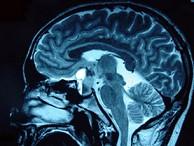

问题 男,47岁,头痛三年余,最近2个月感觉视力下降,MRI检查如图,最可能的诊断为()

选项 A.垂体瘤 B.颅咽管瘤 C.垂体囊肿 D.垂体腺瘤囊变 E.脑膜瘤

答案 D